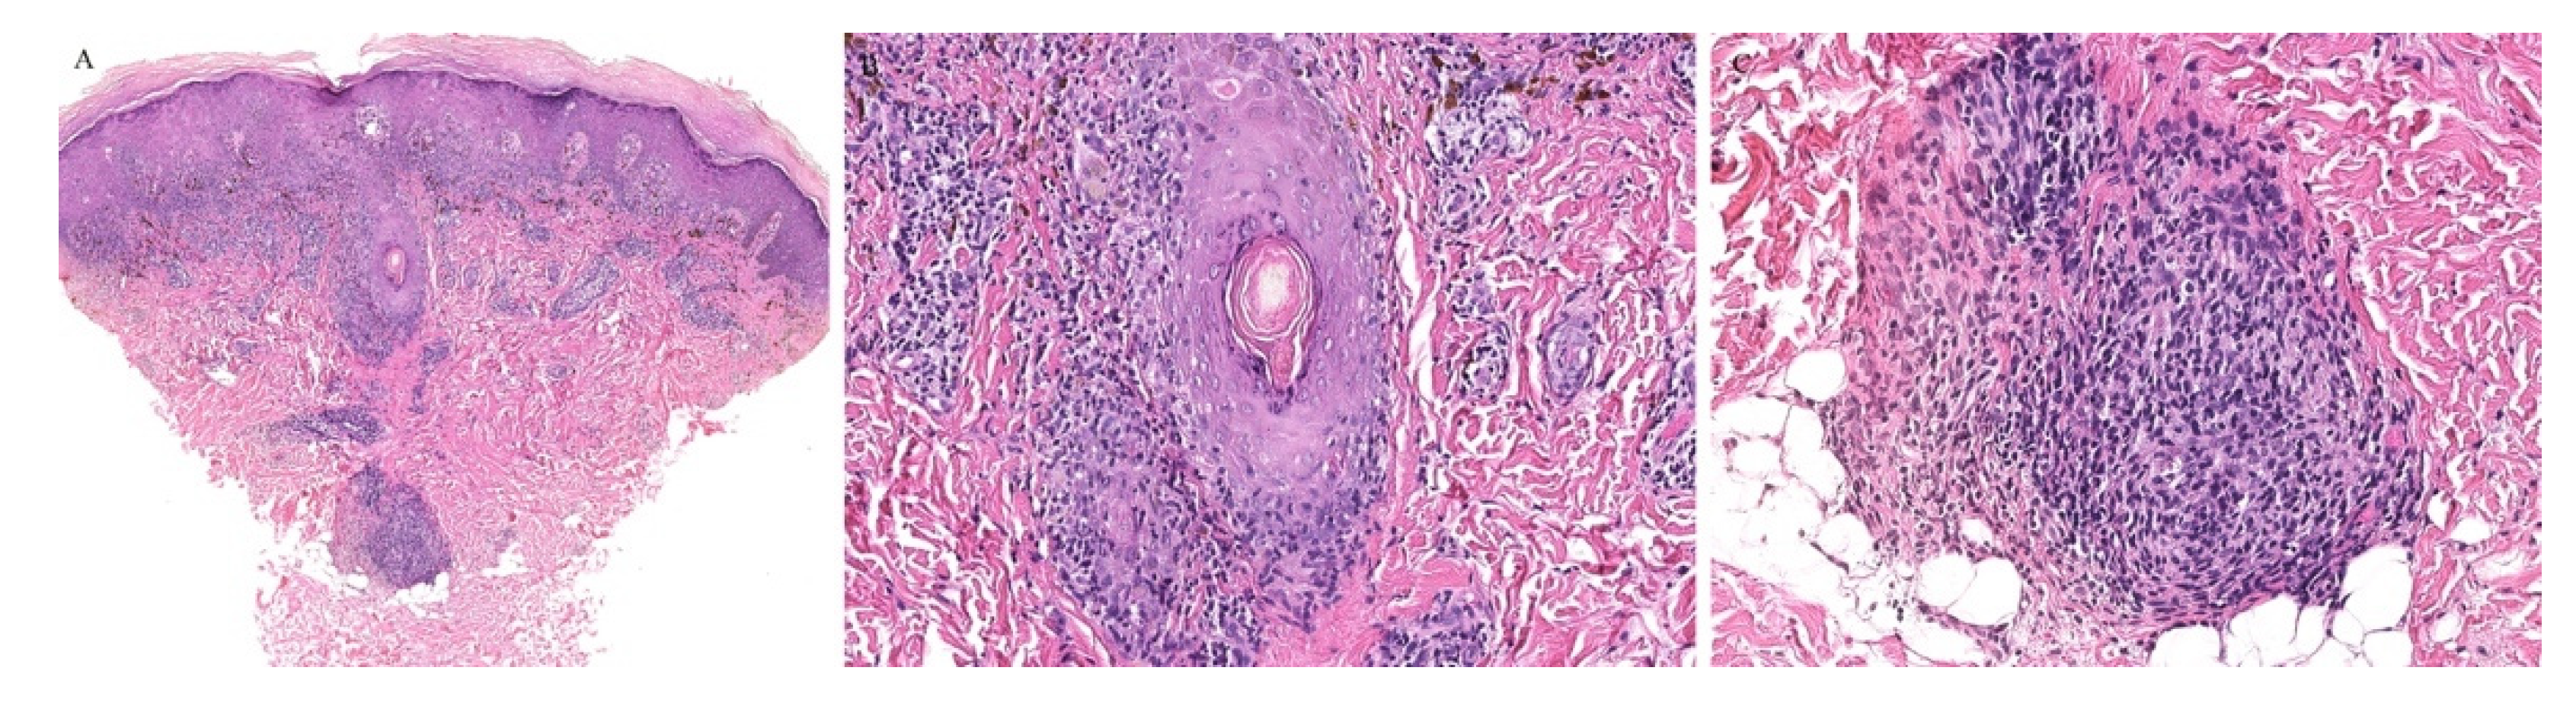

Lichen planus is the prototype lichenoid dermatitis characterized by a self-limiting eruption of pruritic flat-topped violaceous papules. On histopathology, hyperkeratosis, hypergranulosis, irregular acanthosis, and subepidermal clefts known as Max Joseph spaces are observed. A band-like lymphohistiocytic infiltrate is also seen. Distinct adnexotropic variants of lichen planus have been described (Figure 1). These include follicular lichen planus, lichen planus follicularis tumidus, and syringotropic lichen planus.

Lichen planopilaris, or follicular lichen planus, is a distinct variant of lichen planus whereby inflammation is seen around the hair follicle both clinically and histologically (Figure 1). Clinically, this presents with perifollicular erythema, follicular keratotic plugs, and a scarring alopecia [1,2].

Figure 1. (AC) Lichen planus with follicular involvement.